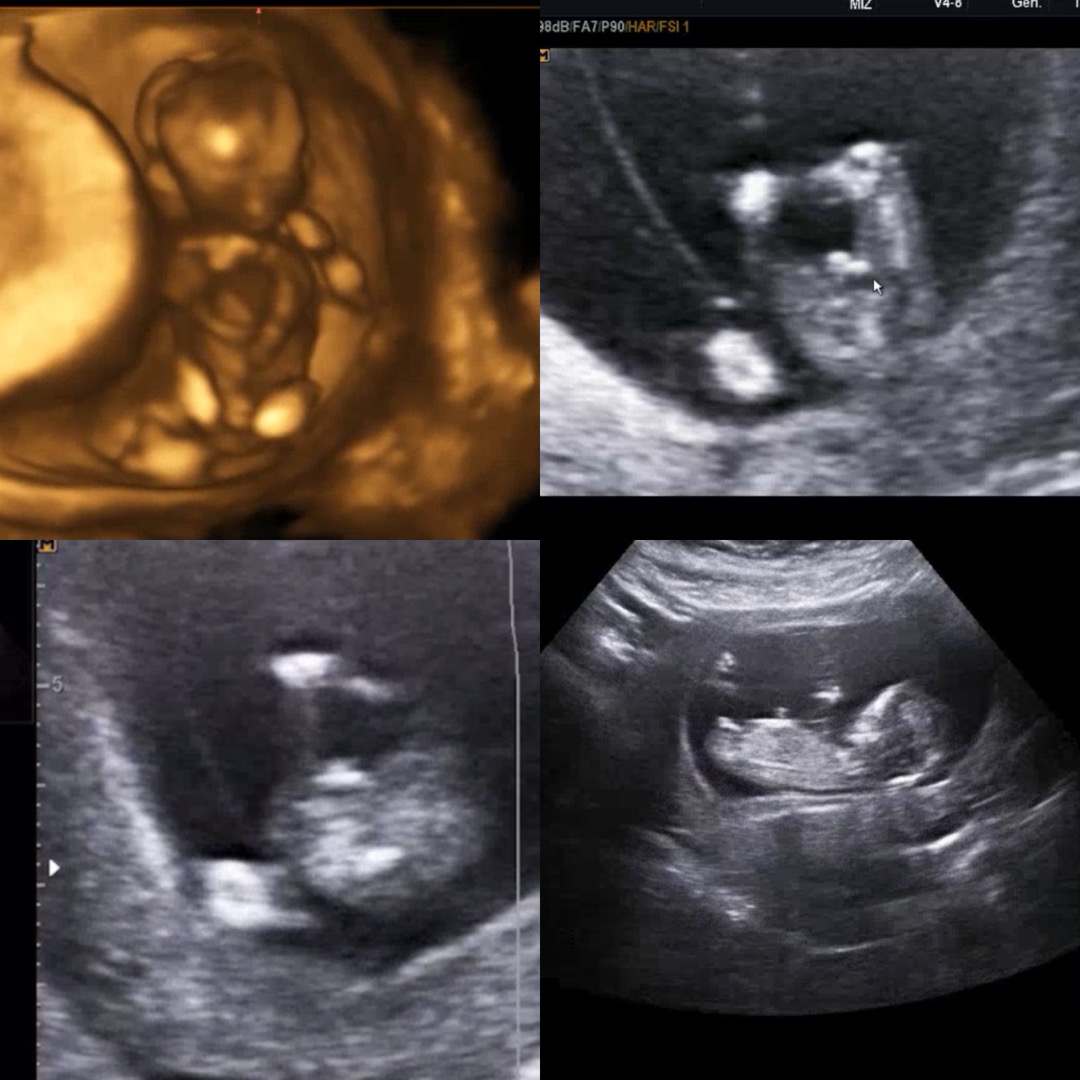

12주 성별 보ㅏ주세요!🫶🏻

둘째인데 병원에서 60프로는 아들이라는데 첫째가 딸이여서 너무 궁금해용!🥲